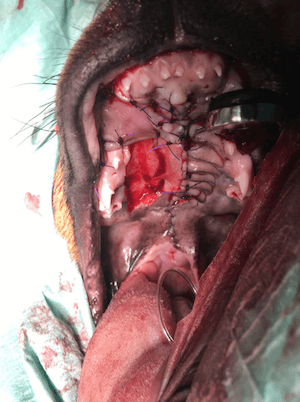

Cleft Palate Repair

In a pup.